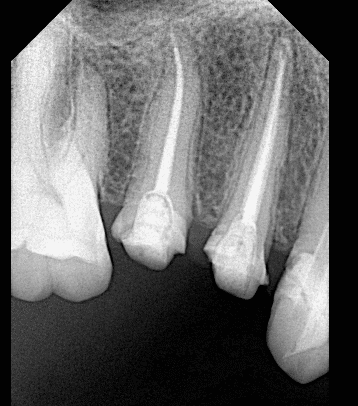

Pre-operative x ray

Cone fitt

After obturation

After preparation

Final x ray